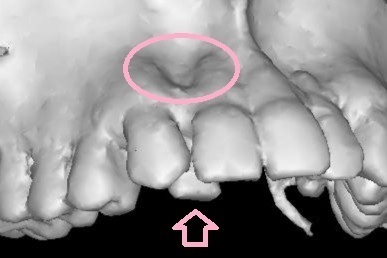

もう一つ大きな注意点があります

初診時に大きく中に入っていた上の右2番目(向かって左側2番目)の前歯

これを理想と思われる位置にもっていきたかったのですが

初診時のCT(3Dのレントゲン)を細かく分析すると

理想の位置に移動させてしまうと

最悪歯が骨から抜けてしまい抜歯に至る可能性がありました

(専門用語でフェネストレーションといいます)

矯正治療をしたことで抜歯に至るというのは本末転倒です

今回は理想の位置よりもわずかに中に入った位置で矯正終了となることを

事前に患者さまにご了承いただいてからスタートしております

現在ではCTとクリンチェックを結合することができるので

もっとわかりやすく確認できるようになっていますが

下にCTの画像を載せておきます

〇部分が骨がないところ 矢印の歯を理想の位置までは動かせません